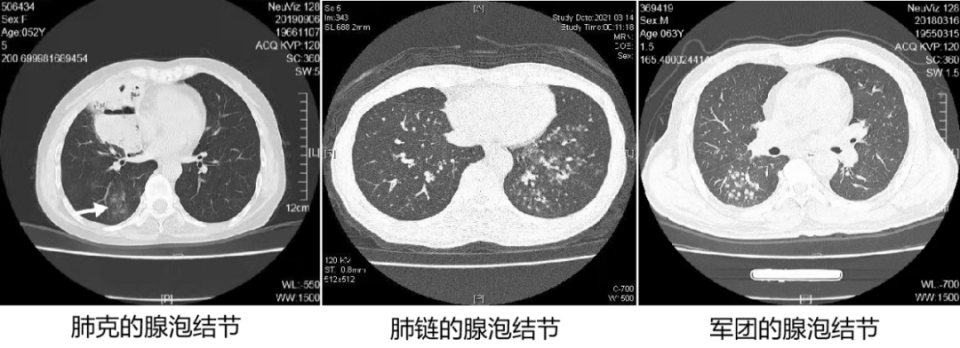

1. 腺泡(acinus):肺腺泡是肺终末支气管远端的结构单位,由Ⅰ级呼吸细支气管供应。它包含了肺泡管和肺泡。它的构成部分都参与气体交换,故它是最大的气体交换单位(肺的基本功能单位)。肺腺泡直径大小约 6~10 mm。一个次级肺小叶含有 3~25 个肺腺泡。

2. 腺泡结节:正常腺泡在 CT 上并不显影,当腺泡因炎症渗出时显影,我们称其为腺泡结节。腺泡结节提示肺泡性肺炎。

1. 肺泡性肺炎(大叶性肺炎):肺炎链球菌肺炎、肺炎克雷伯杆菌肺炎、军团菌肺炎及肺隐球菌病。